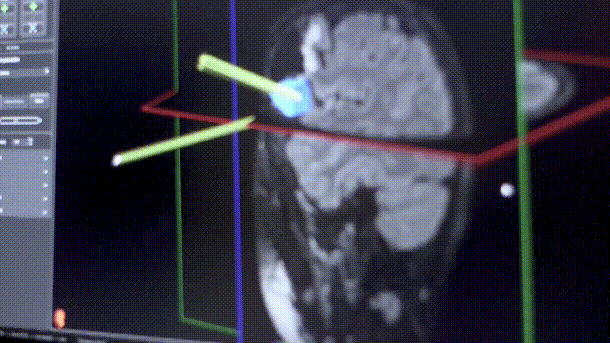

(艾文的左枕叶毛细胞性星形细胞瘤术中影像分析)

经过James T.Rutka教授手术团队的讨论,他们决定对艾文使用无框架立体定向术和术中神经导航手术,以确保他的病变完全切除。,手术结果得偿所愿,全切除也意味着良好的预后。